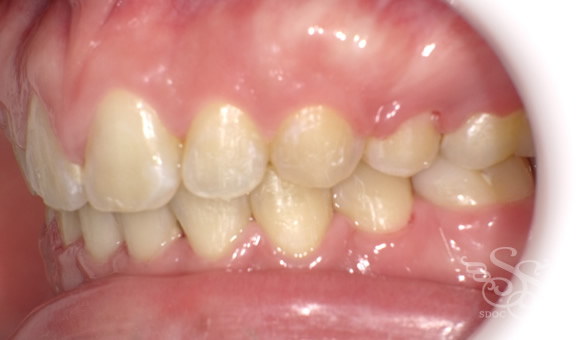

正面:術前

ぱっと見はある程度キレイに並んでいるのですが

前歯がフレアーアウト、前に傾いてしまっています。

口もとの突出感も気になります。